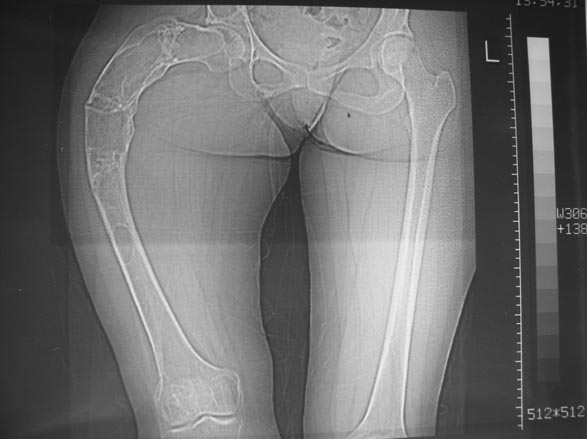

В ноябре этого года я обращался с просьбой о помощи в выборе тактики лечения больной с деформацией бедра на почве фиброзной дисплазии. Были получены интересные и очень полезные советы по операции.

Хотелось бы показать, что получилось в результате.

Операция выполнялась с помощью А.Н.Челнокова. Очень понравилась технология выполнения блокируемого остеосинтеза с использованием спицевого дистрактора, модифицированный гвоздь с латерализованным проксимальным отделом и возможностью многовинтовой фиксации проксимального и дистального участков бедра.